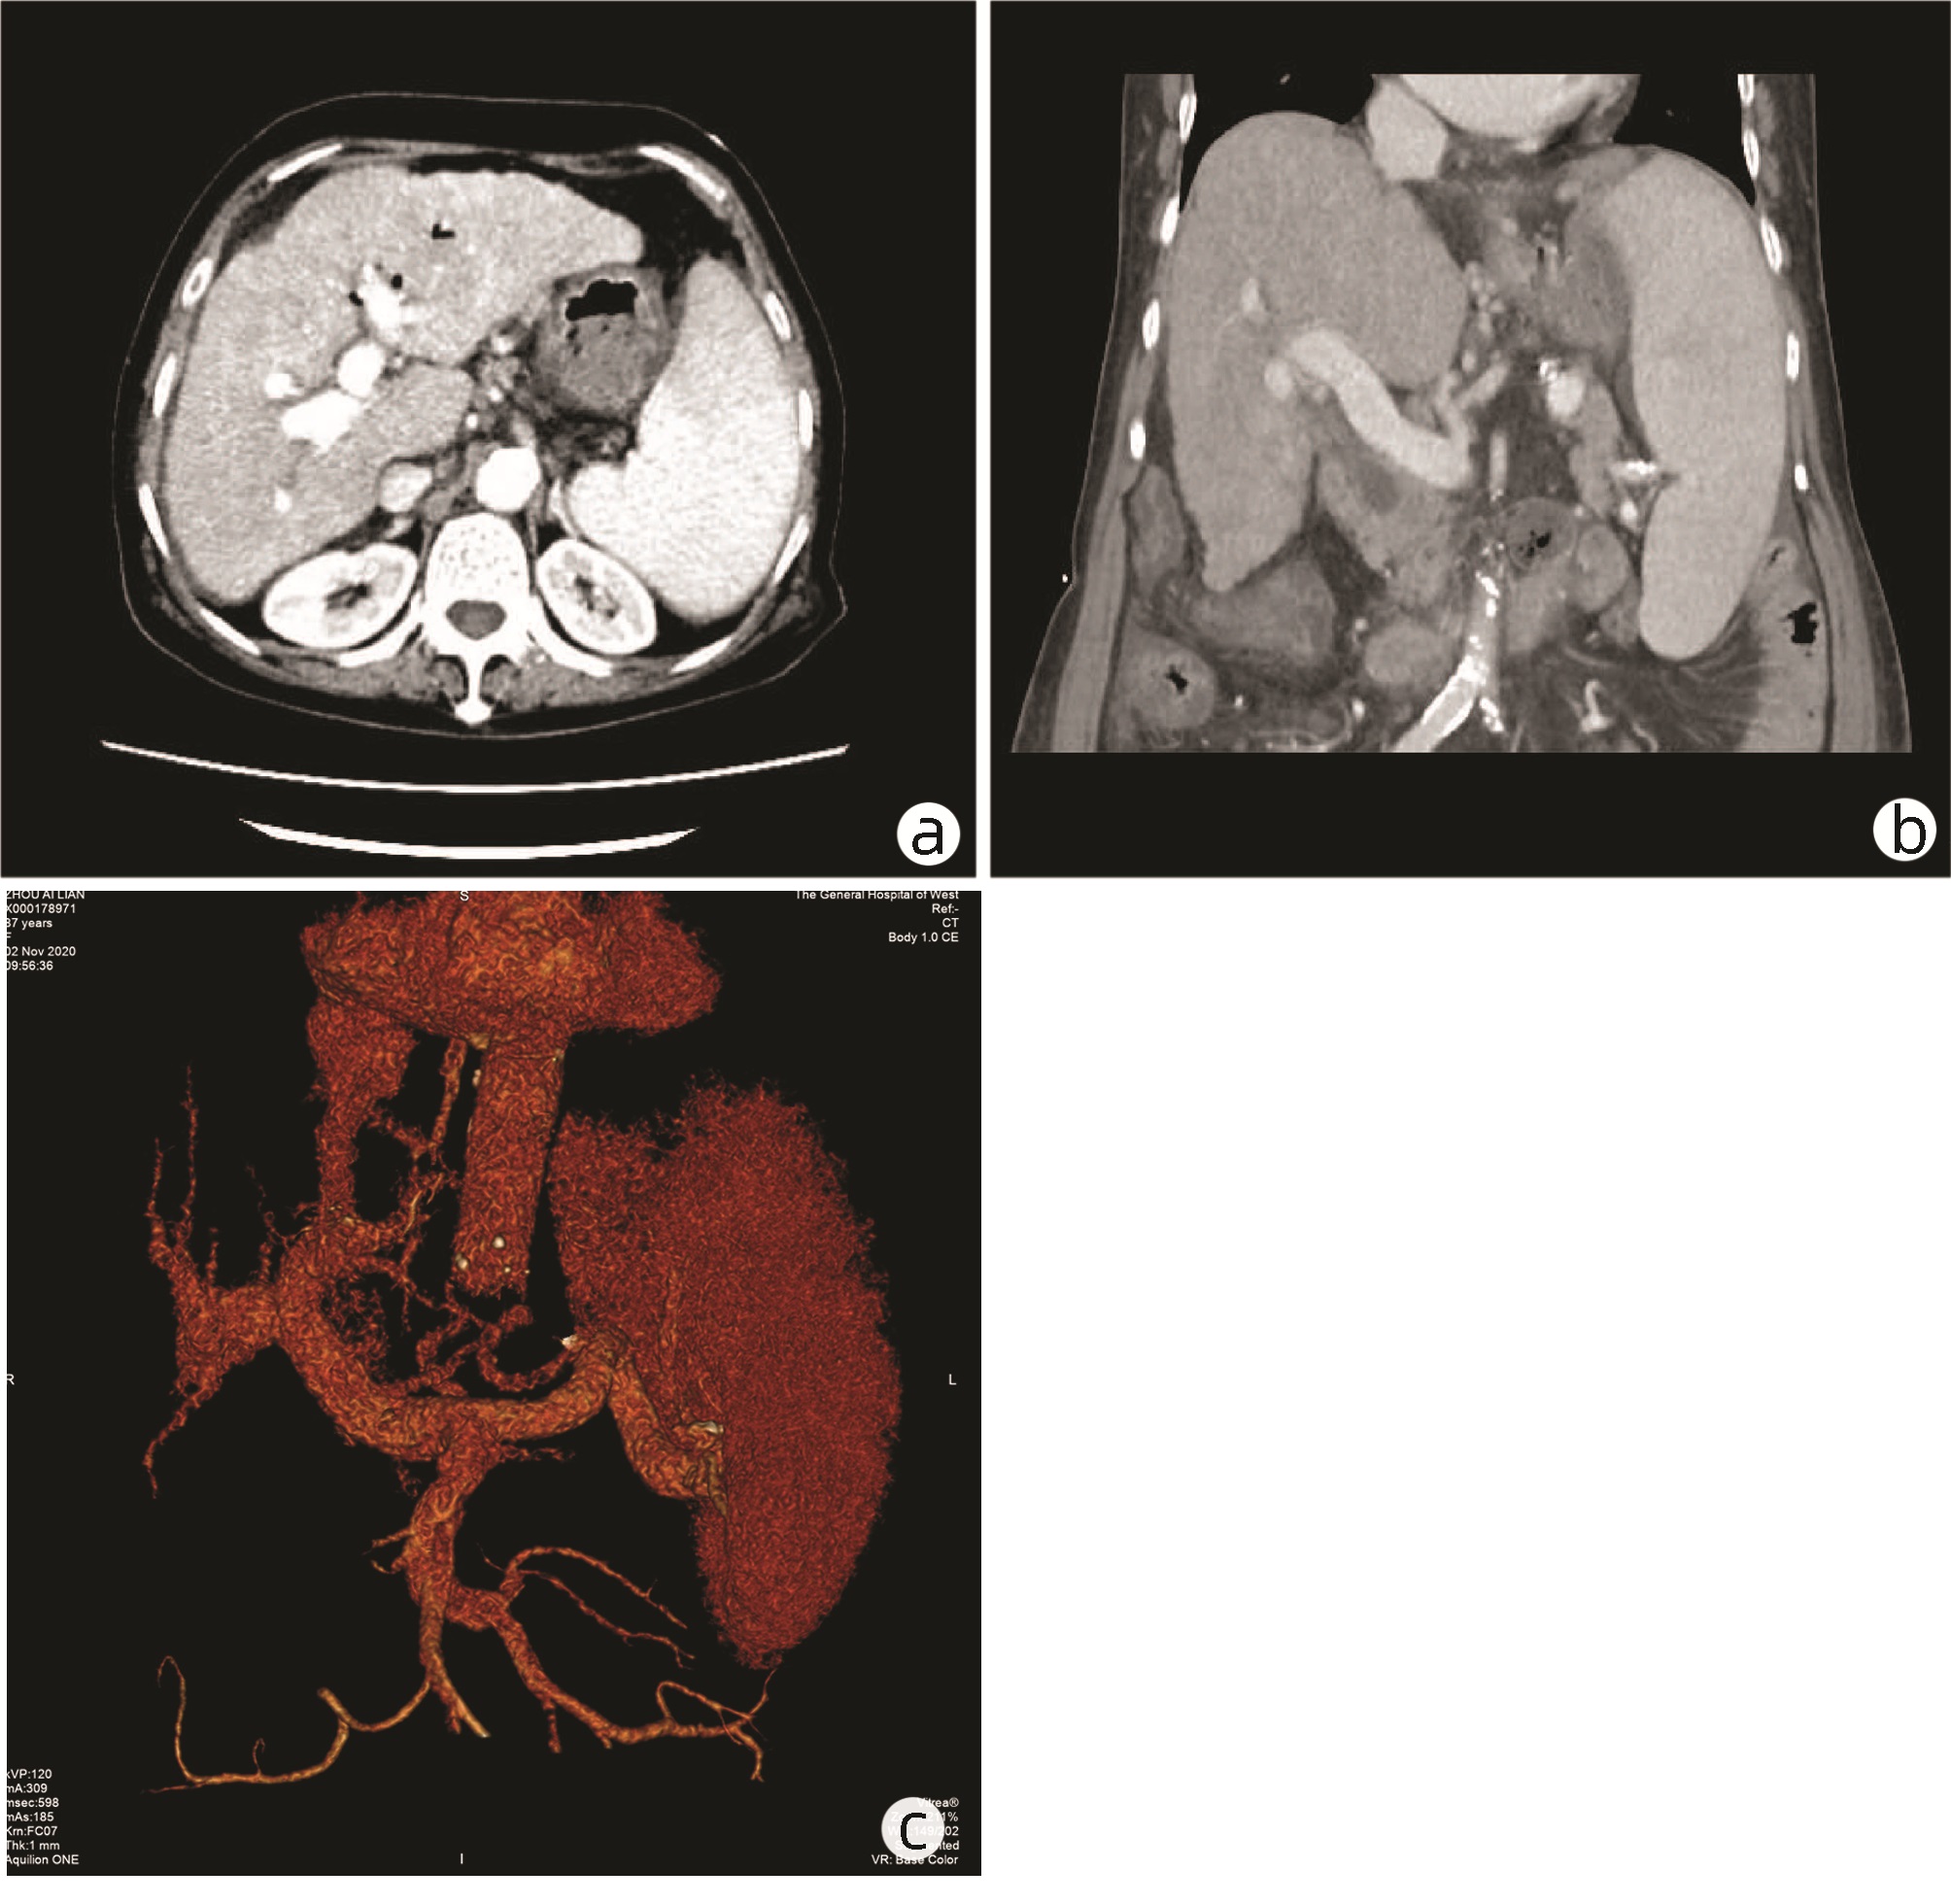

可切除胰腺癌术前评分分级体系的建立与应用

王成方, 王之江, 王伟林

2022, 38(10): 2325-2333. DOI: 10.3969/j.issn.1001-5256.2022.10.023

摘要(1020) HTML (588) PDF (2058KB)(81)

摘要:

目的  探讨分析可切除胰腺癌早期复发的危险因素及评分分级体系的建立与应用。  方法  采用回顾性病例对照研究方法,纳入浙江大学医学院附属第二医院肝胆胰外科2015年3月—2021年6月行根治性切除手术的可切除胰腺癌患者303例,其中283例直接手术患者分为早期复发组(术后6个月内)(n=95)和非早期复发组(n=188);术前行新辅助治疗患者20例为新辅助治疗组。观察指标包括患者的一般资料及术前影像资料;患者术前实验室检验资料,血常规、血生化及衍生指标,肿瘤标志物及凝血指标;随访获得无复发生存情况。正态分布的计量资料两组间比较采用t检验;非正态分布的计量资料两组间比较采用Mann-Whitney U检验。计数资料两组间比较采用χ2检验。通过受试者工作特征曲线确定各指标的最佳临界值。采用多因素Logistic回归分析胰腺癌患者早期复发的危险因素。绘制Kaplan-Meier曲线并采用Log-rank检验比较各组患者的无复发生存期。  结果  单因素分析结果显示,与非早期复发组相比,早期复发组患者BMI、甘油三酯较低,CA19-9、CA242、CA125、血浆纤维蛋白原较高(P值均<0.05)。多因素Logistic回归分析结果显示,BMI(OR=1.150,95%CI:1.038~1.273,P=0.007)、血浆纤维蛋白原(OR=2.513,95%CI:1.355~4.663,P=0.003)和CA242(OR=2.482,95%CI:1.067~5.774,P=0.035)是可切除胰腺癌患者早期复发的独立危险因素。将BMI、CA242、血浆纤维蛋白原3项指标纳入评分分级体系,临界值分别为23.00 kg/m2、30.00 U/mL和4.00 g/L。BMI<23.00 kg/m2计为1分,否则计为0分;CA242≥30.0 U/mL计为1分,否则0分;血浆纤维蛋白原≥4.00 g/L计为1分,否则0分,总分为0~3分。对早期复发与非早期复发患者进行评分,结果显示早期复发组评分更高[2(0~3)分vs 1(0~3)分,Z=-5.339,P<0.001]。Kaplan-Meier曲线分析结果显示,不同评分组别的患者无复发生存时间比较差异有统计学意义(χ2=28.116,P<0.001),分值越高预期无复发生存时间越短。将3分定义为高危组,0~2分定义为低危组。高危组早期复发率为84.6%,低危组早期复发率为31.2%。  结论  基于BMI、血浆纤维蛋白原和CA242这3项指标建立的评分系统能够在一定程度上预测患者术后复发情况。